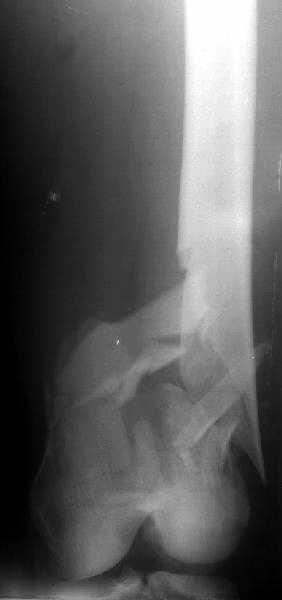

The discussed case was pure metaphyseal, not T- or Y- intraarticular.

Though the second case was C2 fracture, and it took to perform closed reduction with joystick wires, and then insert opposite olive wires.

DMI> Please enlighten about your technique, positioning of pt. ,Type of table,

A small wire distractor was used for intra op reduction. Position - supine with adduction and internal rotation of the affected limb.